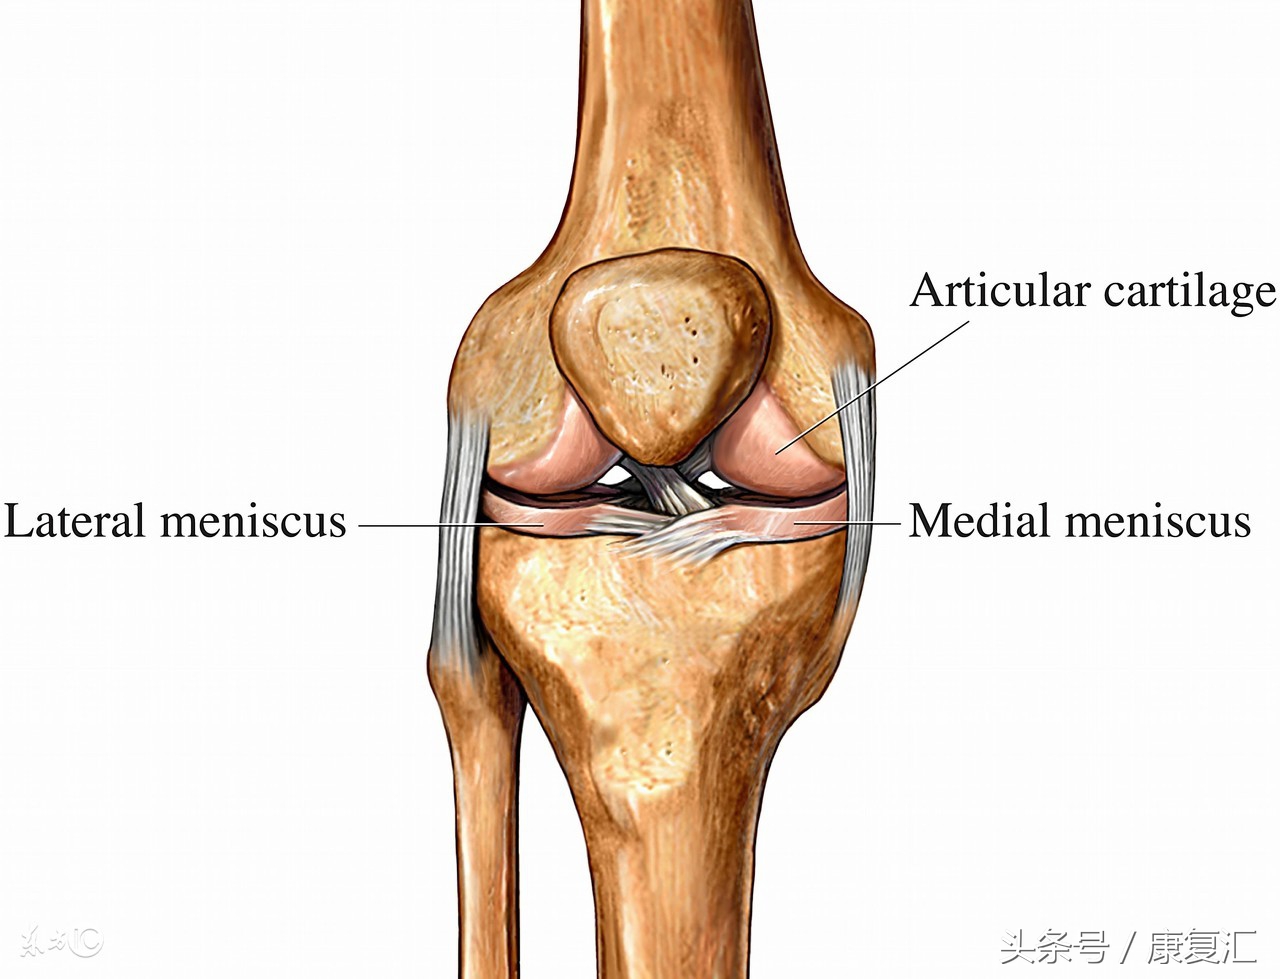

膝关节内侧副韧带(Medial Collateral Ligament,MCL)是膝关节内侧稳定的主要结构,又称胫侧副韧带,起自内收肌结节下方的股骨内上髁,延伸至前胫骨结节,止于胫骨内侧髁内侧。分为深浅两层,深层与关节囊紧密相连,浅层与内侧半月板紧密相连。当膝关节伸直时,内侧副韧带紧张;当膝关节半曲时,内侧副韧带松弛,从而稳定膝关节限制其外翻和旋转,MCL是在膝关节屈曲位时防止膝关节外翻的关键因素。

根据损伤的部位还可以分为接近大腿侧的断裂,接近小腿侧的断裂和中间断裂。临床中单纯的膝关节副韧带损伤很少,往往伴有膝关节其它软组织如内侧半月板、前交叉韧带和关节囊的损伤,并发症的发生率为73%。